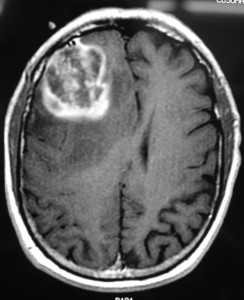

Глиобластома: симптомы, выявляемые с помощью МРТ. Аксиальный срез в режиме Т1 после контрастирования препаратом гадолиния демонстрирует распространенную опухоль правой лобной доли. Изображение предоставлено доктором George Jallo.

МРТ того же пациента. Т2-взвешенное изображение демонстрирует то же поражение, что и на предыдущем рисунке с заметным отеком и смещением срединных структур. Эти находки соответствуют высокой степени злокачественности опухоли.